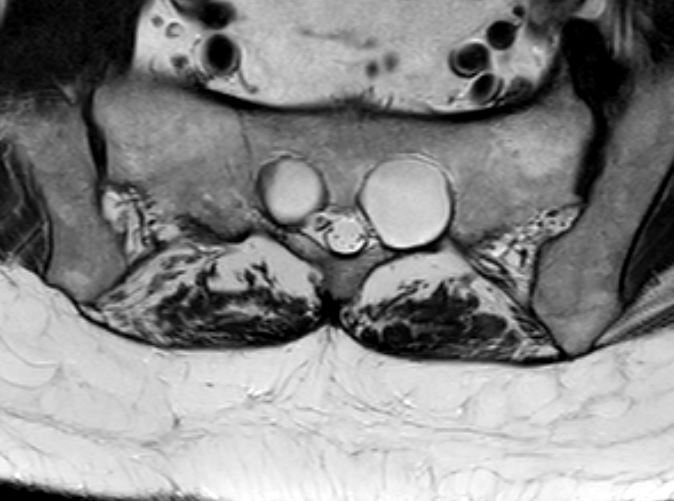

Bilateral sacral perineural cysts

Bilateral sacral perineural cysts on axial MRI in a T2 sequence.